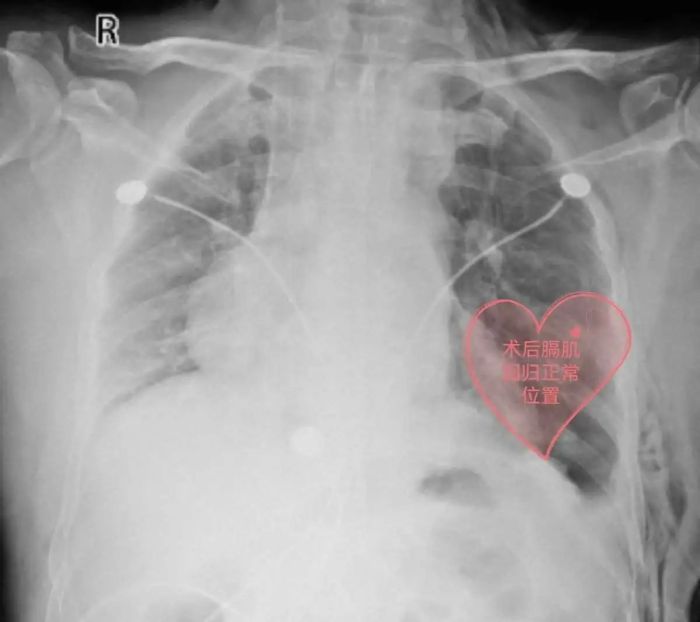

入院后第4天,心胸外科团队经过充分的术前准备,在全麻下为李先生行电视胸腔镜微创膈肌折叠缝合术,术后各项指征恢复正常,顺利出院。出院后,爬坡上楼再也不累了、不喘了,一口气走上4楼也没问题。